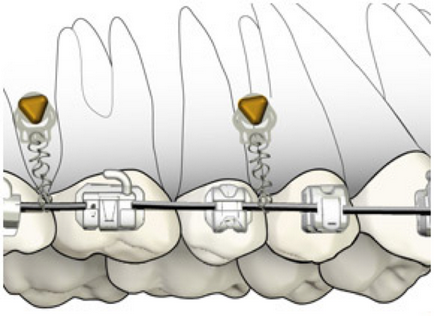

Fogszabályozó kezelés. Még kifejezettebb fogíny mosoly, hogy gyakran jön, hogy segítsen a fogszabályozó kezelés. Szerelőkengyele rendszer mikrocsavarokkal lehetővé teszi, hogy végre egy bizonyos szegmense az állkapocs és jelentősen javítja a helyzetet.